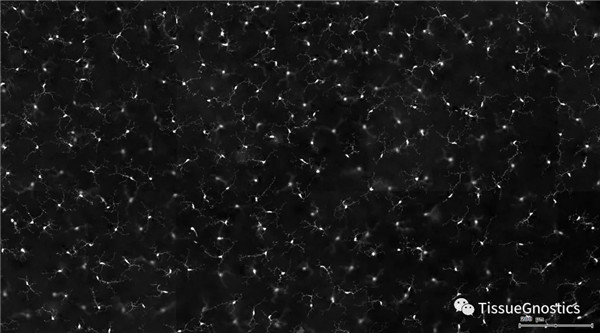

單通道灰階圖(↑:FITC,↓:Texa Red)

視網(wǎng)膜熒光樣本中小膠質(zhì)細(xì)胞胞體、神經(jīng)纖維識(shí)別、血管識(shí)別、血管斑點(diǎn)識(shí)別、神經(jīng)元與血管的距離分析。

一般而言,眼底圖像通常都是通過激光掃描成像進(jìn)行采集,但是由于眼底可觀測(cè)的視野往往是很有限的,一個(gè)患者的眼底信息需要多張掃描圖像才能完全顯示出來。這種局限性大大不利于病情進(jìn)行全面的、細(xì)致的診斷。Tissue Cytometry全景組織流式定量分析技術(shù)進(jìn)行全景圖像獲取,在單細(xì)胞、組織結(jié)構(gòu)、細(xì)胞空間信息等多個(gè)層面進(jìn)行定位、定性、定量分析。從而更好的對(duì)病變區(qū)域進(jìn)行有針對(duì)性的跟蹤觀察和全面分析。